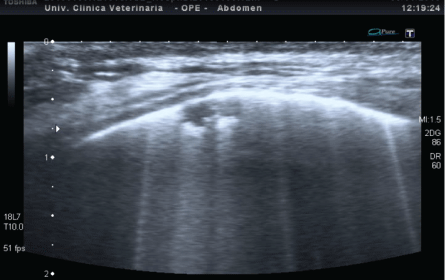

19例肺泡间质综合征患者有b线,但有两种不同的胸膜模式:

图4:ARDS患者胸膜线不规则增厚和胸膜下实变的b线超声检测(与图2相比)。